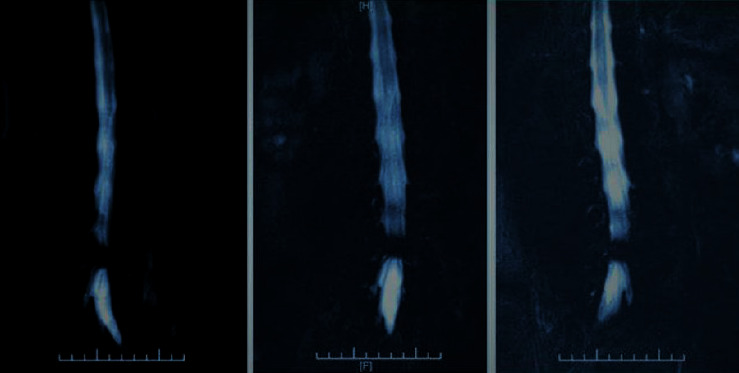

The treatment of lumbar disc herniation is mainly to enable athletes to train the athletes themselves with the help of rehabilitation therapists to improve the blood circulation and nutritional levels inside the lumbar spine joints, and strengthen the power imbalance of the lumbar and abdominal functional muscle groups so that the internal physiological structure of the lumbar vertebra is repaired to a certain extent, and a new state of balance and stability of the neuromuscular is finally formed to realize the normal physiological function of the lumbar vertebra joint. Therefore, rehabilitation training is mainly performed in three stages during the injury recovery process. In the first phase of the plan, clinical methods were mainly used to alleviate the pain and limited joint movement of athletes during the acute phase of waist injury. In the second phase, attention was paid to the activation of neuromuscular muscles and the correction of movement patterns. The content of intensive rehabilitation training is because the intensity of the initial training is not great. The third stage helps athletes perform the neuromuscular reconstruction. Rehabilitation training of lumbar disc herniation has different goals, training methods, and principles at different stages. Changes in lumbar swelling values at three different times are shown in Figure 3.

Figure 3.

Changes in swelling values on days 1, 3, 5, 7, 10, and 14 of patients in the three groups.

From Figure 3, it can be seen that during the treatment of the three groups of patients with lymphedema after joint replacement, the circumference of the affected limbs changed. After 3 days of treatment, there was no significant difference in the improvement of the circumference of the limbs in the three groups (#P > 0.05). After 7, 7, 10, and 14 days, the three groups of cases all had a certain effect on the improvement of limb circumference (℧℧P < 0.05 and ▽P < 0.01), but the effect was more significant in the Chinese and Western medicine group, which was better than the single Chinese medicine group and the Western medicine group (◎P < 0.01 and ◎◎P < 0.01). Comparing the age of the two groups of patients, after t test, t = 0.759, P=0.451 > 0.05, the difference was not statistically significant, indicating that the age distribution of the two groups of patients is comparable. The comparison of age between the two groups is shown in Table 5.